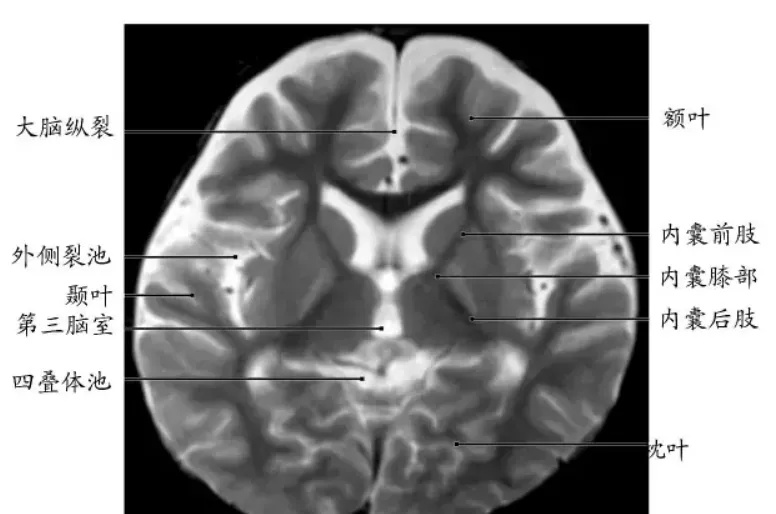

大脑基底节区图片

基底节区是医学影像学名词。包括:基底节及其周围白质、内囊。为一不太明确的区域。内囊,概念很明确,包括内囊前肢、内囊膝部及内囊后肢。

现代磁共振系统,不断发展,具有很高的软组织对比。但即使如此,仍然难以准确区分是基底节与邻近白质,因此,影像医生可能会将此宽泛地描写成“基底节区“。它其实既包括了基底节神经核团,也包括了它邻近的白质纤维。

内囊前肢位于尾状核与豆状核之间,上行纤维是丘脑内侧核至额叶皮质的纤维(丘脑前辐射),下行纤维是额叶脑桥束(额桥束);内囊膝部位于前、后肢相连处,皮质延髓束于此通过;内囊后肢位于丘脑与豆状核之间,依前后顺序分别为皮质脊髓束(支配上肢者靠前,支配下肢者靠后)、丘脑至中央后回的丘脑皮质束(丘脑中央辐射),其后为听辐射、颞桥束、丘脑后辐射和视辐射等。